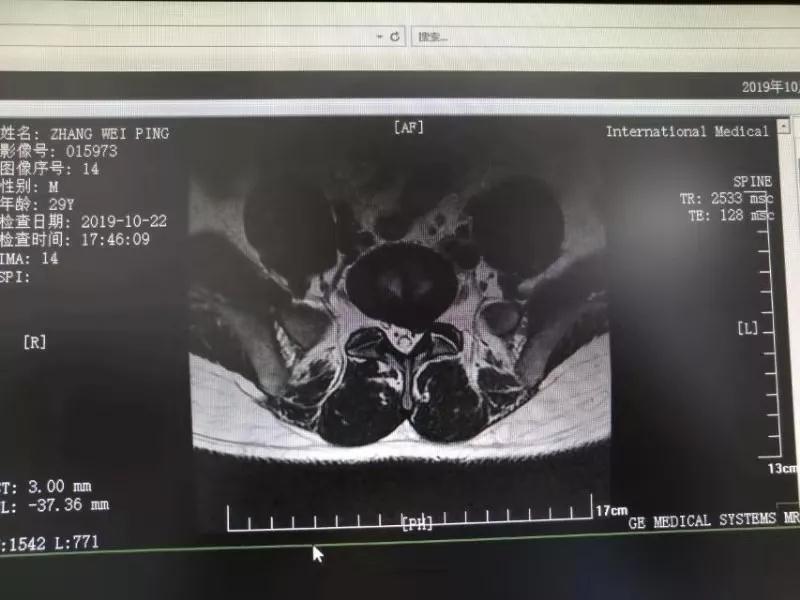

10月25日,29歲的患者小張了解到西安國際醫(yī)學(xué)中心骨科醫(yī)院專家云集,一大早便在家人的陪同下,來到西安國際醫(yī)學(xué)中心骨科醫(yī)院就診?!拔已闯掷m(xù)2年多,最近感冒后腰痛癥狀明顯加重了?!毙埫媛犊喑?,因?yàn)殚L期腰痛、左下肢放射性疼痛,她晚上睡覺不能平躺,經(jīng)常疼得睡不著,需要口服止痛藥物才能有所緩解。走路走不了多遠(yuǎn)就開始腿抽的疼,嚴(yán)重影響到工作和生活。

結(jié)合患者的檢查以及年齡情況,王自立副院長推薦讓專門研究椎間孔鏡技術(shù)王雄勛主任給小張做微創(chuàng)的椎間孔鏡手術(shù)。該手術(shù)創(chuàng)傷很小,不影響脊柱的穩(wěn)定性,尤其適合于椎間盤突出的年輕患者,懷著對(duì)骨科醫(yī)院專家的信任,小張與家人商議后,接受手術(shù)治療。